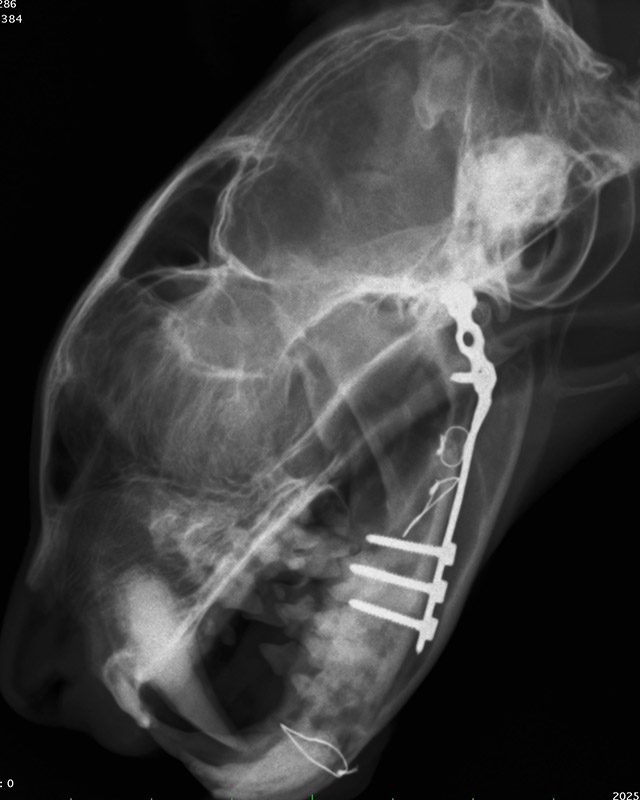

下顎骨骨折

雑種猫(14歳)

犬に咬まれた

手術前

手術後